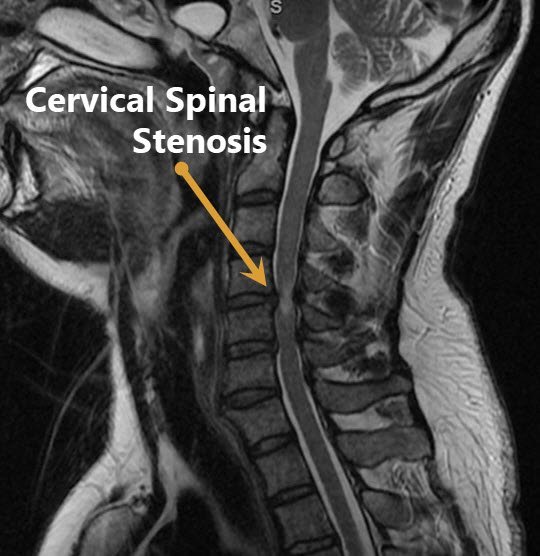

What is Cervical Stenosis?

Cervical stenosis is narrowing around the spinal cord or nerve roots that exit the spine in the neck.

The nervous structures (nerve roots or spinal cord) get compressed by other structures such as:

- Intervertebral disc material

- Bone spurs

- Joint cysts

- Tumors or Infections (less common)